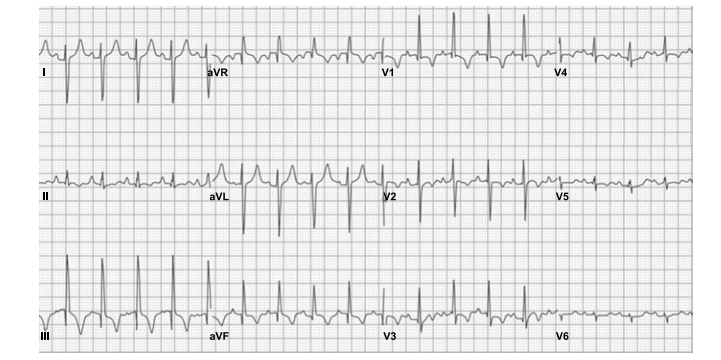

Leia o enunciado a seguir e responda a questão.

Paciente do sexo feminino, 66 anos, com antecedentes de tabagismo, hipertensão arterial sistêmica e diabetes mellitus tipo 2, procura atendimento médico com queixa de desconforto retroesternal tipo queimação e opressão que se iniciou há 1 mês, desencadeado aos grandes esforços. Há 1 semana passou a apresentar os mesmos sintomas em repouso, associados à dispneia, com duração de até 8 minutos e melhora espontânea. A paciente faz uso de valsartana 80 mg, glimepirida 4 mg e metformina 1000 mg. O exame físico é normal, PA = 150x85 mmHg e frequência cardíaca de 96 bpm. O eletrocardiograma está ilustrado a seguir.

Provas

Leia o enunciado a seguir e responda a questão.

Paciente do sexo feminino, 66 anos, com antecedentes de tabagismo, hipertensão arterial sistêmica e diabetes mellitus tipo 2, procura atendimento médico com queixa de desconforto retroesternal tipo queimação e opressão que se iniciou há 1 mês, desencadeado aos grandes esforços. Há 1 semana passou a apresentar os mesmos sintomas em repouso, associados à dispneia, com duração de até 8 minutos e melhora espontânea. A paciente faz uso de valsartana 80 mg, glimepirida 4 mg e metformina 1000 mg. O exame físico é normal, PA = 150x85 mmHg e frequência cardíaca de 96 bpm. O eletrocardiograma está ilustrado a seguir.

Provas

Homem, 46 anos, com antecedente de infarto agudo do miocárdio, é portador de miocardiopatia isquêmica e insuficiência cardíaca. Atualmente recebe tratamento otimizado para insuficiência cardíaca, no entanto permanece em classe funcional III (NYHA). O ecocardiograma mostra diâmetro diastólico do ventrículo esquerdo = 72 mm e fração de ejeção do VE = 34%. Holter de 24 horas: extrassístoles ventriculares frequentes, quatro episódios de taquicardia ventricular não sustentada e um episódio de taquicardia ventricular sustentada com 1 minuto de duração. O eletrocardiograma está ilustrado a seguir.

Assinale a alternativa correta em relação à redução de morbimortalidade do paciente em questão.